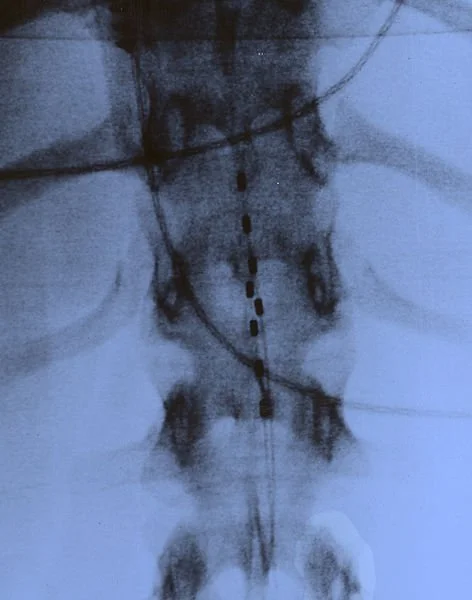

If you heard a lot of buzz coming out of Switzerland in early February about the results of a new Epidural Electrical Stimulation clinical trial involving three men with a spinal cord injury, you may have wondered just what exactly is all the fuss about this latest approach to help recover lost function after an SCI. Our friends at Spinalpedia have developed a page that would educate you on how this approach is being used and how it works which you can read HERE.